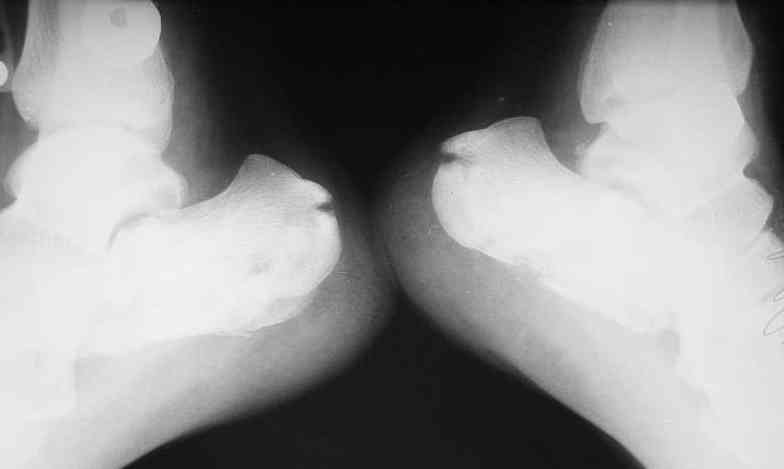

> Перелом левой седалищной кости без смещения с нарушением

> функции тазовых органов.

Нарушение функции тазовых органов связано с переломом седалищной кости без смещения??? ...или это опечатка, и функция тазовых органов относится к спинальному повреждению? Тогда, почему нестабильный перелом L3 - неосложненный?

Сегодня пациент мочится самостоятельно. Консультирован неврологом. Неврологического дефицита не найдено. Сила в конечностях сохранена, снижена слева в нижней конечности из-за болей в паховой области. В свете последних решений "партии и правительства", будем накладывать реклинирующий корсет и готовить к "отплытию". Грустно, так как этот, совсем не соотечественник, стал мне глубоко симпатичен: очень мужественный молодой человек.

ЗЫ: В приложении снимок таза.